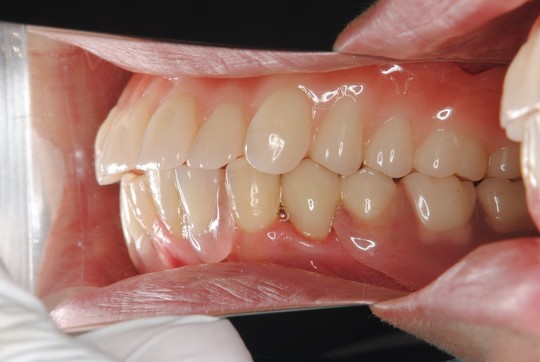

治療後

金属の金具が見えなくなり審美性がとても良くなりました。特に笑った時の顔に自信がもてます。

入れ歯に関しては金具が目立たない入れ歯にして欲しいとの要望がありましたので下の部分入れ歯をノンクラスプ義歯で製作しました。また、しっかりと安定して噛めるようにするため義歯は金属フレームで補強しました。

※上顎はBPS義歯を製作しました。

※下顎左右小臼歯はセラミックスクラウン修復を行いました。